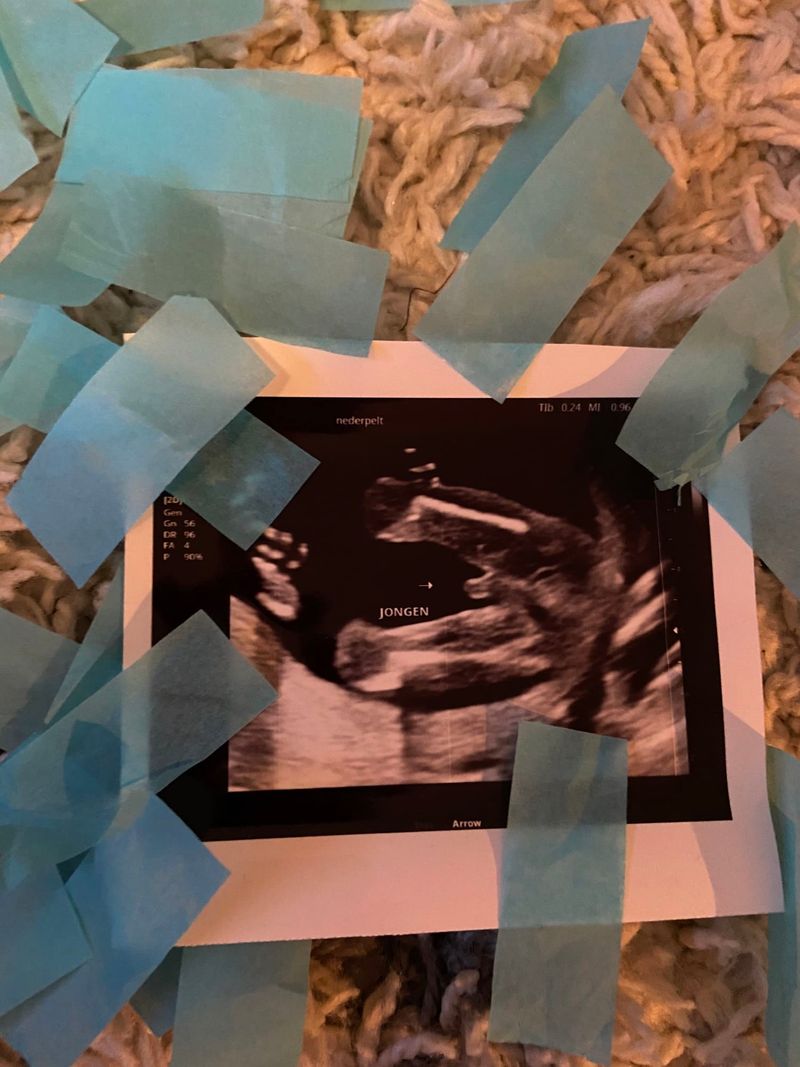

Het geslacht

Dinsdagavond 8 december was de echo bij de verloskundige. Er werd naar het geslacht gekeken. Alles zag er goed uit. Blij en opgelucht. We kregen het geslacht in een enveloppe en de juiste kleur confettikanonnen mee.

Het was Kerstavond. Alle vier stonden we met onze confettikanon klaar. De kamer kleurde met blauwe confetti. “Zie je: een jongen”, dacht ik. Ach en zijn broers waren zo blij. Een broertje, dat hoopten ze zo! Wie had gedacht dat nog geen week later ons leven compleet op zijn kop zou staan. Na een leuke kerst in coronastijl, fantaseerden we over de kerst volgend jaar met de kleine erbij. Ik voelde hem inmiddels ook echt heel goed bewegen. Aan de buitenkant voelde je dit ook. Het heerlijkste gevoel dat er bestaat.